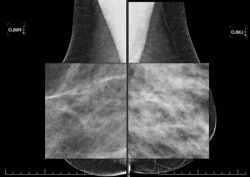

La mammographie est une radiographie des seins. Elle utilise des rayons X. En matière d’irradiation des patients, aucun risque n’a pu être démontré compte tenu des faibles doses utilisées et des précautions prises pour limiter au strict minimum la zone examinée. Toutefois, pour les femmes enceintes, des précautions doivent être prises systématiquement : c’est pourquoi il est important de signaler si vous pouvez être dans ce cas. Pour la qualité de l’image et une moindre irradiation, il est nécessaire de comprimer le sein. Afin de diminuer l’inconfort de la compression, il est conseillé de faire cet examen en première partie de cycle menstruel.

L’examen comporte 2 ou 3 clichés sur chaque sein. La compression du sein est nécessaire pour améliorer la qualité des clichés, donc l'efficacité du diagnostic radiologique. La compression est un peu désagréable. Elle est très rarement douloureuse.

En fonction de l'orientation de votre examen, mais aussi de la texture plus ou moins dense de vos seins, une échographie pourra être nécessaire ; celle-ci viendra alors compléter votre examen.